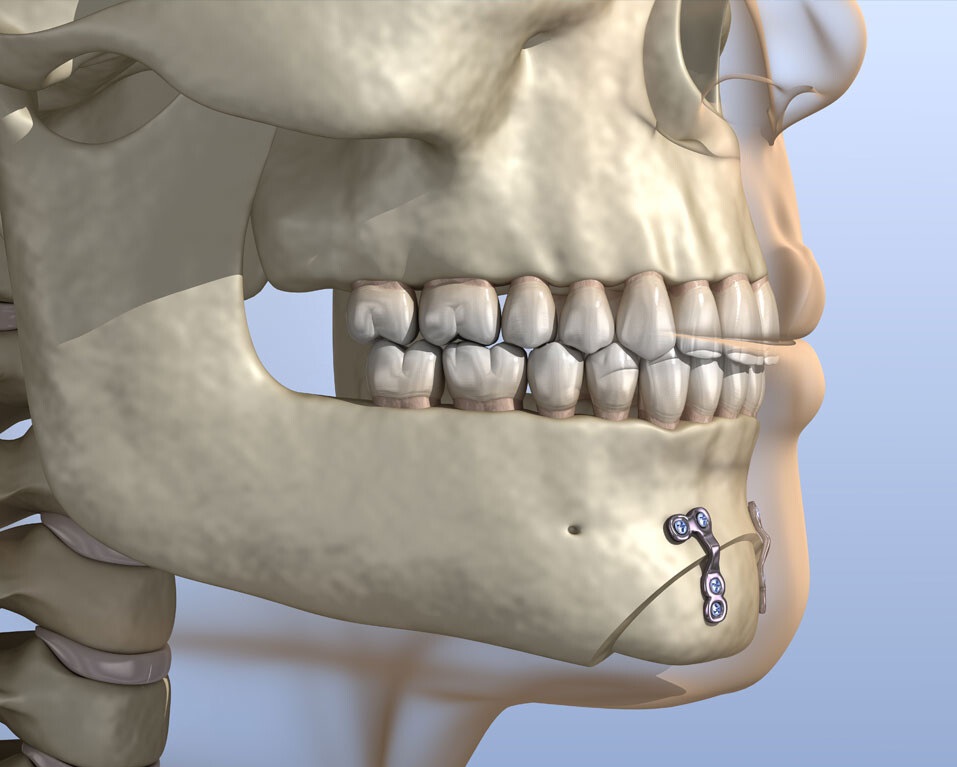

جراحی چانه؛ بهبود تقارن فک و زیبایی صورت

جراحی چانه (ژنیوپلاستی) برای اصلاح اندازه، شکل و موقعیت چانه انجام میشود. این عمل با بزرگ کردن، کوچک کردن یا تغییر شکل چانه، به بهبود تناسب صورت و افزایش اعتماد به نفس کمک میکند و میتواند مشکلات زیبایی یا عملکردی فک را برطرف نماید.